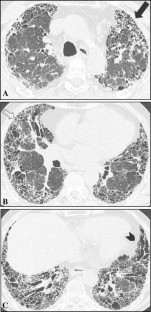

Fig. 3